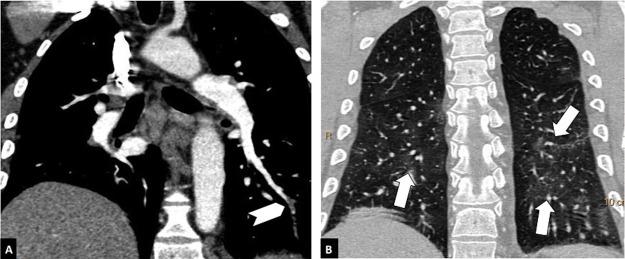

To determine the prevalence of pulmonary embolism in patients with COVID-19; to determine the possible relationship between the severity of pulmonary involvement and D-dimer levels; to analyze the location of pulmonary embolisms in patients with COVID-19 and to compare it with the location in patients without COVID-19.

We included 492 pulmonary CT angiograms (342 (69.9%) in patients with COVID-19 and 147 (30.1%) in patients without COVID-19). The prevalence of pulmonary embolisms was higher in patients with COVID-19 (26% vs. 16.3% in patients without COVID-19, p=0.0197; relative risk=1.6). The prevalence of pulmonary embolisms in the same period in 2019 was 13.2%, similar to that of the group of COVID-19-negative patients in 2020 (p=0.43). There were no significant differences in D-dimer levels or the location of pulmonary embolisms between the two groups. CT showed moderate or severe pulmonary involvement in 78.7% of the patients with COVID-19.

确定 COVID-19 患者中肺栓塞的患病率;确定肺受累严重程度与 D-二聚体水平之间的可能关系;分析 COVID-19 患者肺栓塞的位置,并与无 COVID-19 患者的位置进行比较。

共纳入 492 例肺动脉 CT 血管造影(COVID-19 患者 342 例[69.9%],无 COVID-19 患者 147 例[30.1%])。COVID-19 患者肺栓塞的患病率较高(26%比无 COVID-19 患者[16.3%],p=0.0197;相对风险=1.6)。2019 年同期的肺栓塞患病率为 13.2%,与 2020 年无 COVID-19 患者组相似(p=0.43)。两组患者的 D-二聚体水平或肺栓塞位置无显著差异。CT 显示 COVID-19 患者中有 78.7%存在中度或重度肺受累。